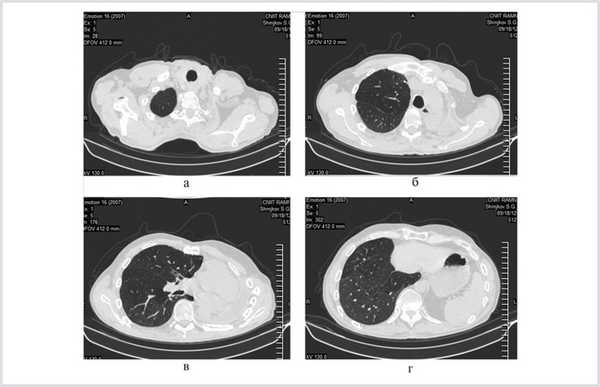

При компьютерной томограмме выявлены цирротические изменения левого легкого с обширной полостью эмпиемы и множественными мелкими полостями в коллабированном легком. Правое легкое уменьшено в объеме за счет фиброзных изменений верхней доли, в которой определялись три каверны диаметром до 2 см, имелось очаговое обсеменение нижних долей (рис. 1).

Рис. 1. Компьютерные томограммы больного Ш. до операции.

При контрольном обследовании 27.02.13 (через 1 год и 6 мес после последней операции) состояние больного удовлетворительное, обострений туберкулеза не было. При многократных исследованиях мокроты МБТ не найдено. При компьютерной томографии отмечены рассасывание и уплотнение очагов в единственном резецированном легком (рис. 4).

Рис. 4. Компьютерные томограммы больного Ш. через 1 год и 6 мес после завершения хирургического лечения.